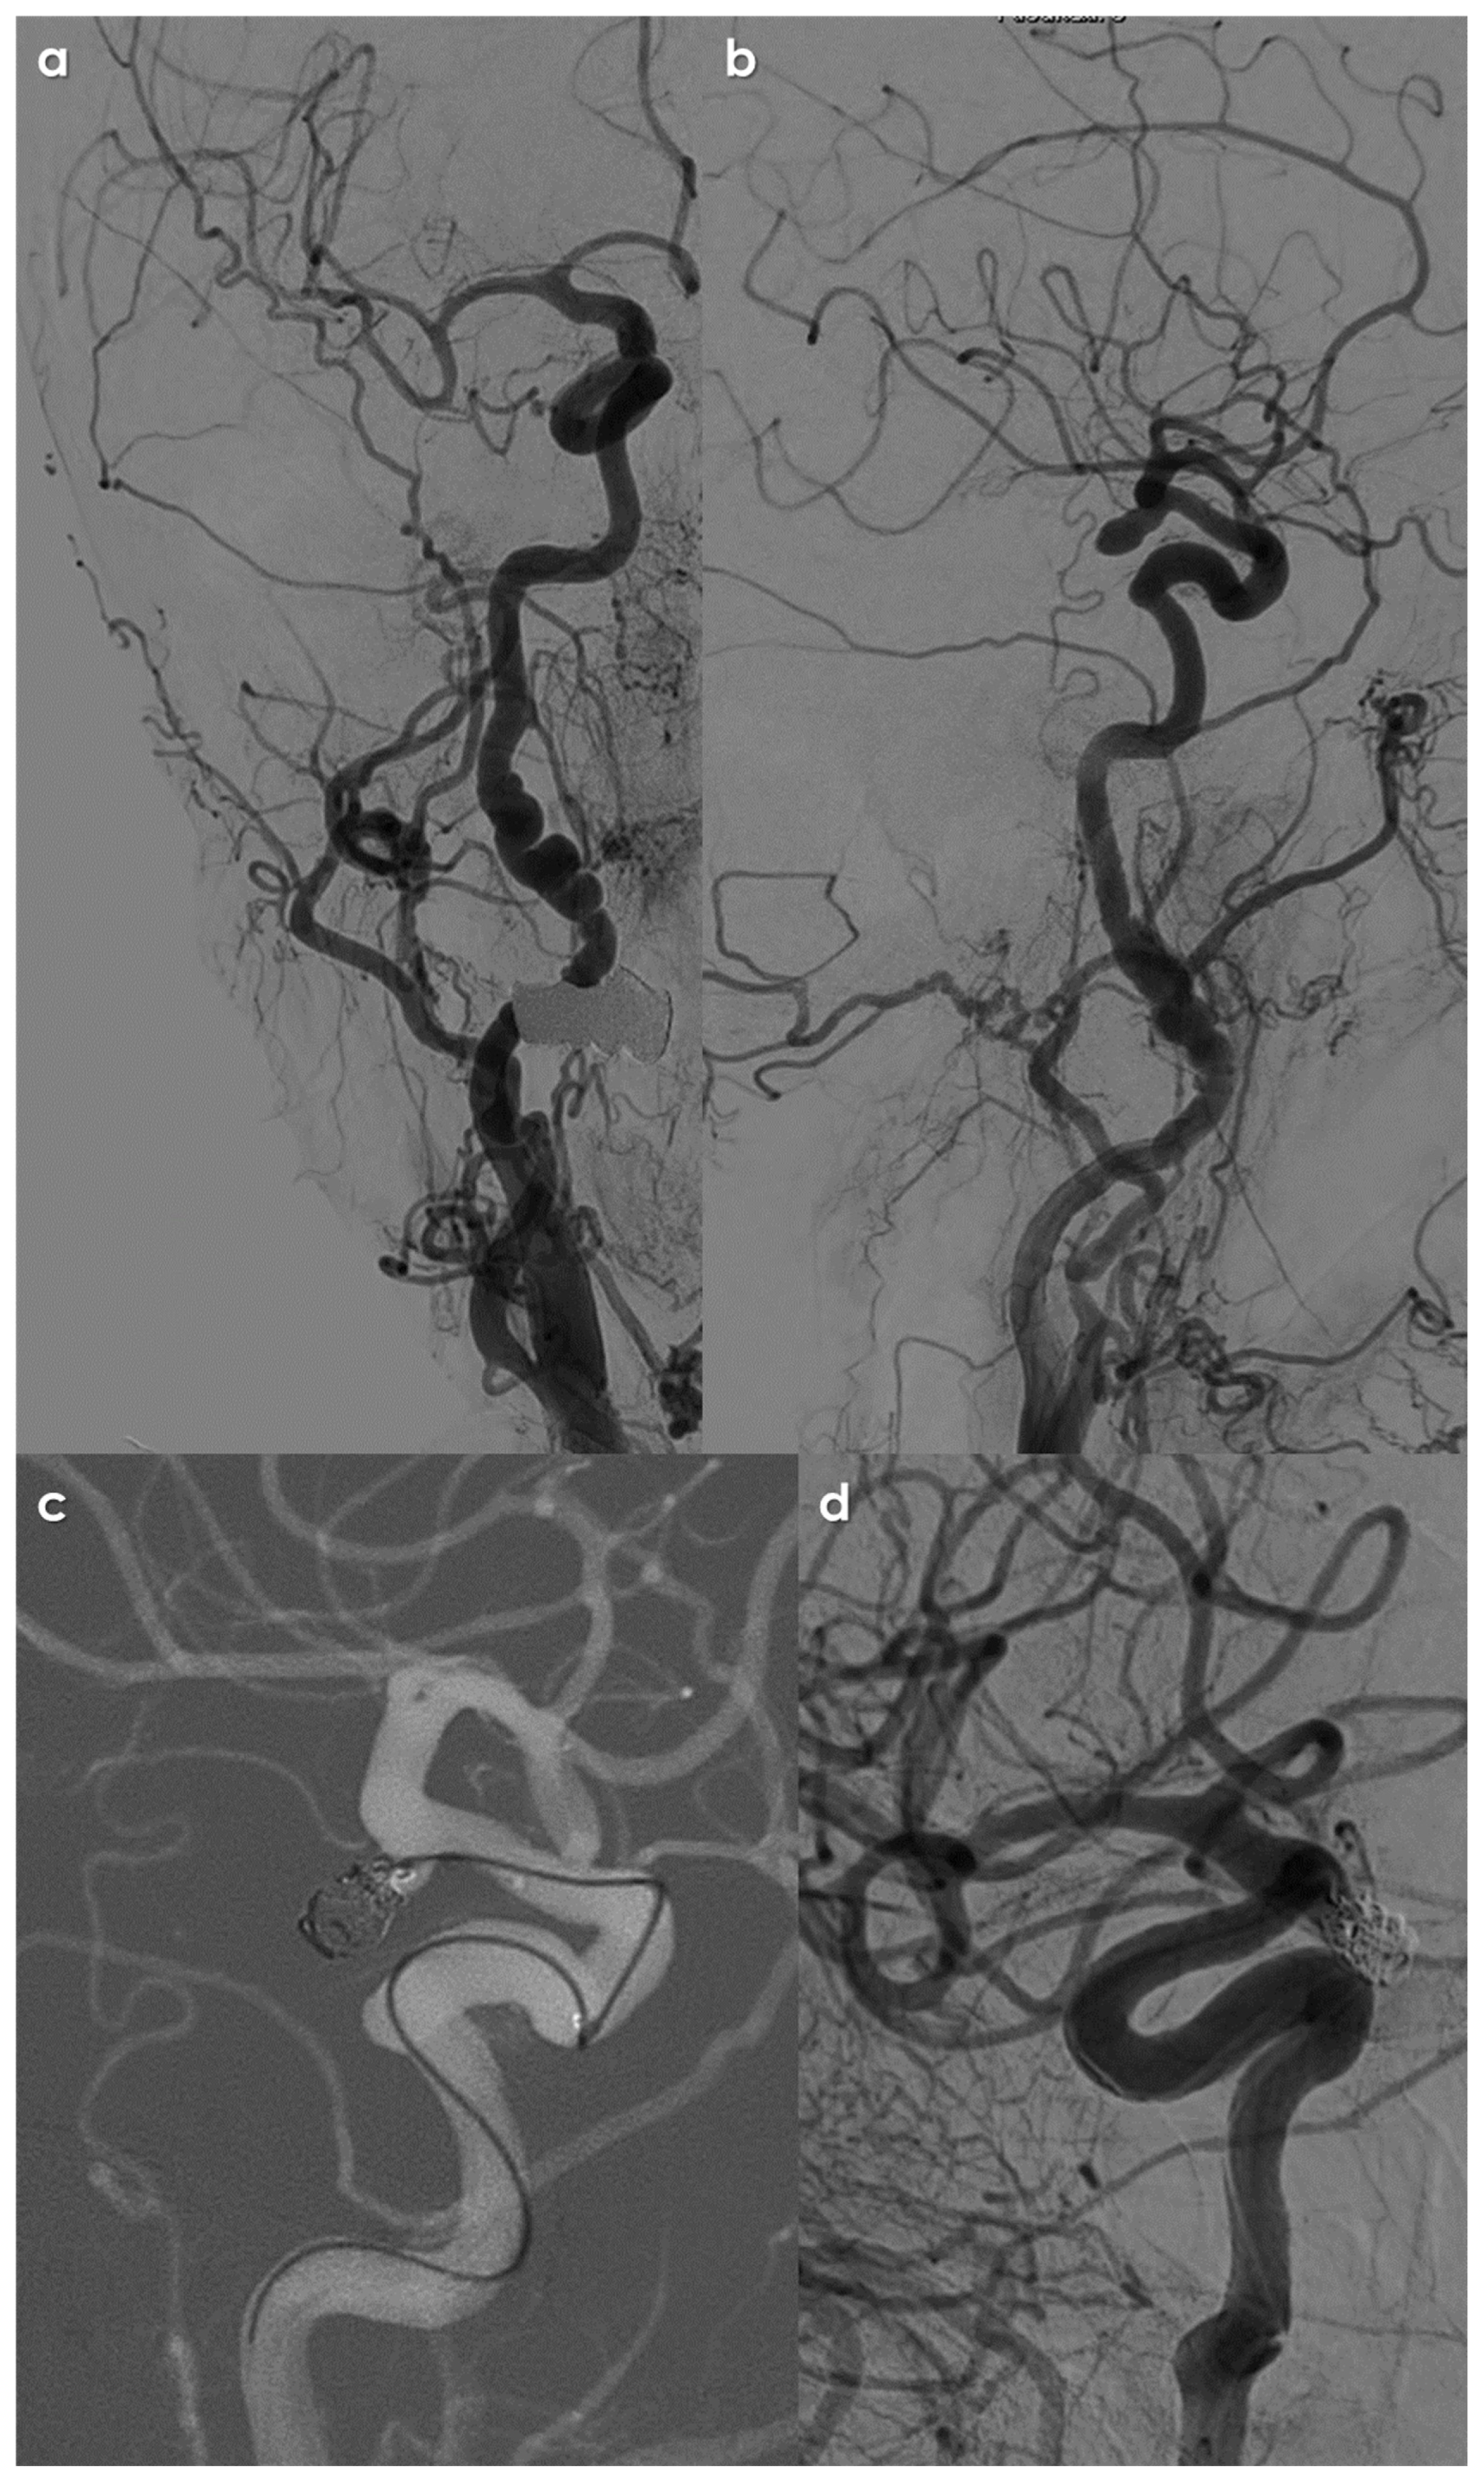

2. Materials and Methods

3. Results

3.4. Treatment Issues